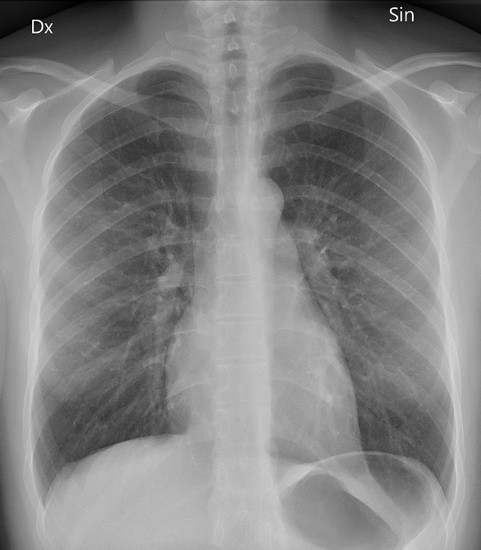

X-quang ngực thẳng số hoá:

X-quang ngực thẳng số hoá Là kỹ thuật phổ biến nhất, sử dụng tia X để tạo ra hình ảnh của xương và các cơ quan nội tạng. Phát hiện được các bất thường sớm trong lồng ngực như:

Bệnh phổi: viêm phổi, viêm phổi do lao, giãn phế quản, u, .…

Bệnh tim: bóng tim lớn, bệnh val tim, …

Hình 1. Chụp X-quang ngực thẳng số hoá.

Hình 2. X-quang ngực thẳng bình thường